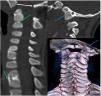

Los estudios de neuroimagen muestran anomalías óseas de la unión occipitovertebral, columna cervical y dorsal (fig. 2), sugestivas de síndrome de Klippel-Feil, que justifican el cuadro. Este síndrome congénito se caracteriza por la fusión vertebral cérvico-dorsal, pudiendo asociar otras malformaciones y alteraciones neurológicas.